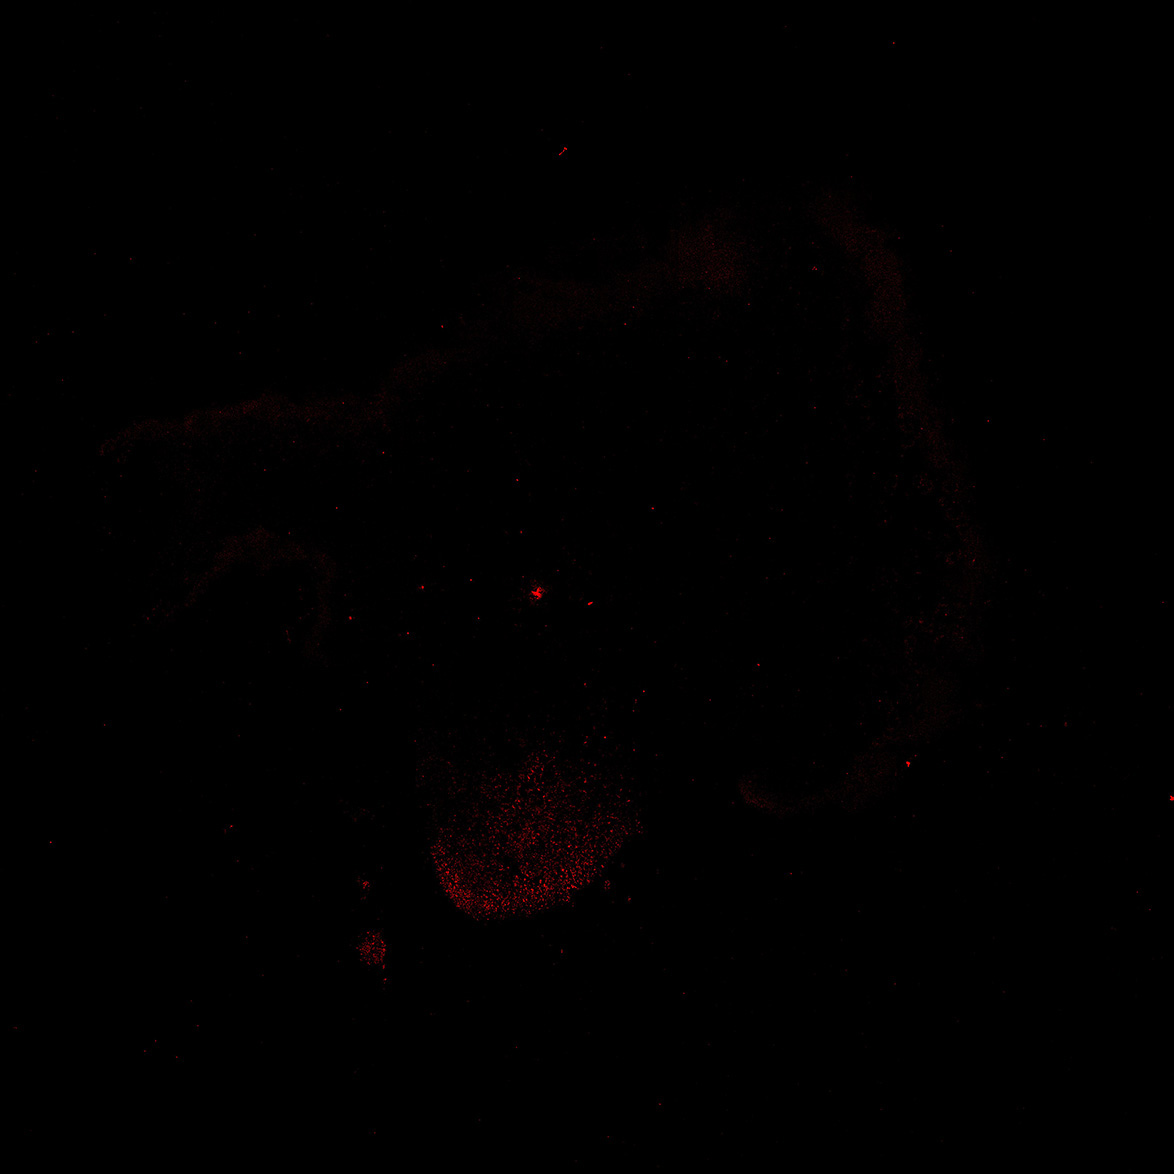

TH

6PCW human midbrain